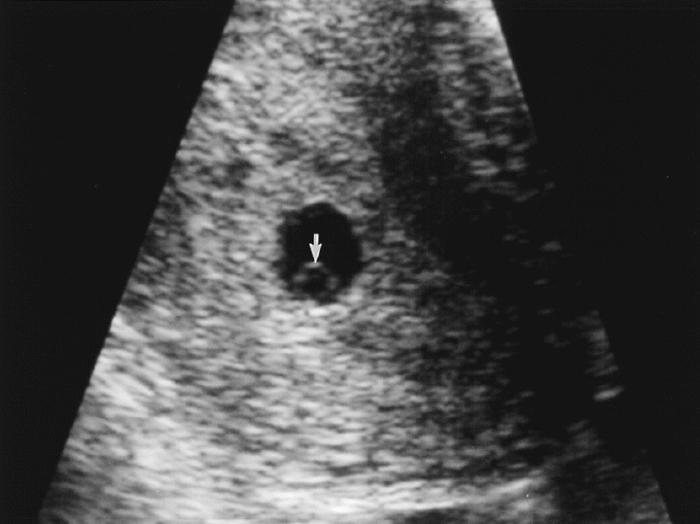

УЗИ, КТГ, доплервсем хорошего дня и самочувствия💋Нам 5,5 недель акушерских )История загадочная про беременность,позже напишу пост,когда услышу заветный звук сердечка!А сейчас меня интересует вот что Была я на УЗИ вчера(рекомендация врача) ,сказали все соответсвует сроку,через 10 дней контроль эмбриончика и СБ,ну а пока только ПЯ 6*7мм))Спросила про ЖМ,мне узист сказал,что он с эмбрионом появится,но на снимке я вижу его)хах)может и бред,но посмотрите,кто нибудь кроме меня видит кружочек?))я уже все фильтры освоила,ну просто Иниересно и не более того))фото воть